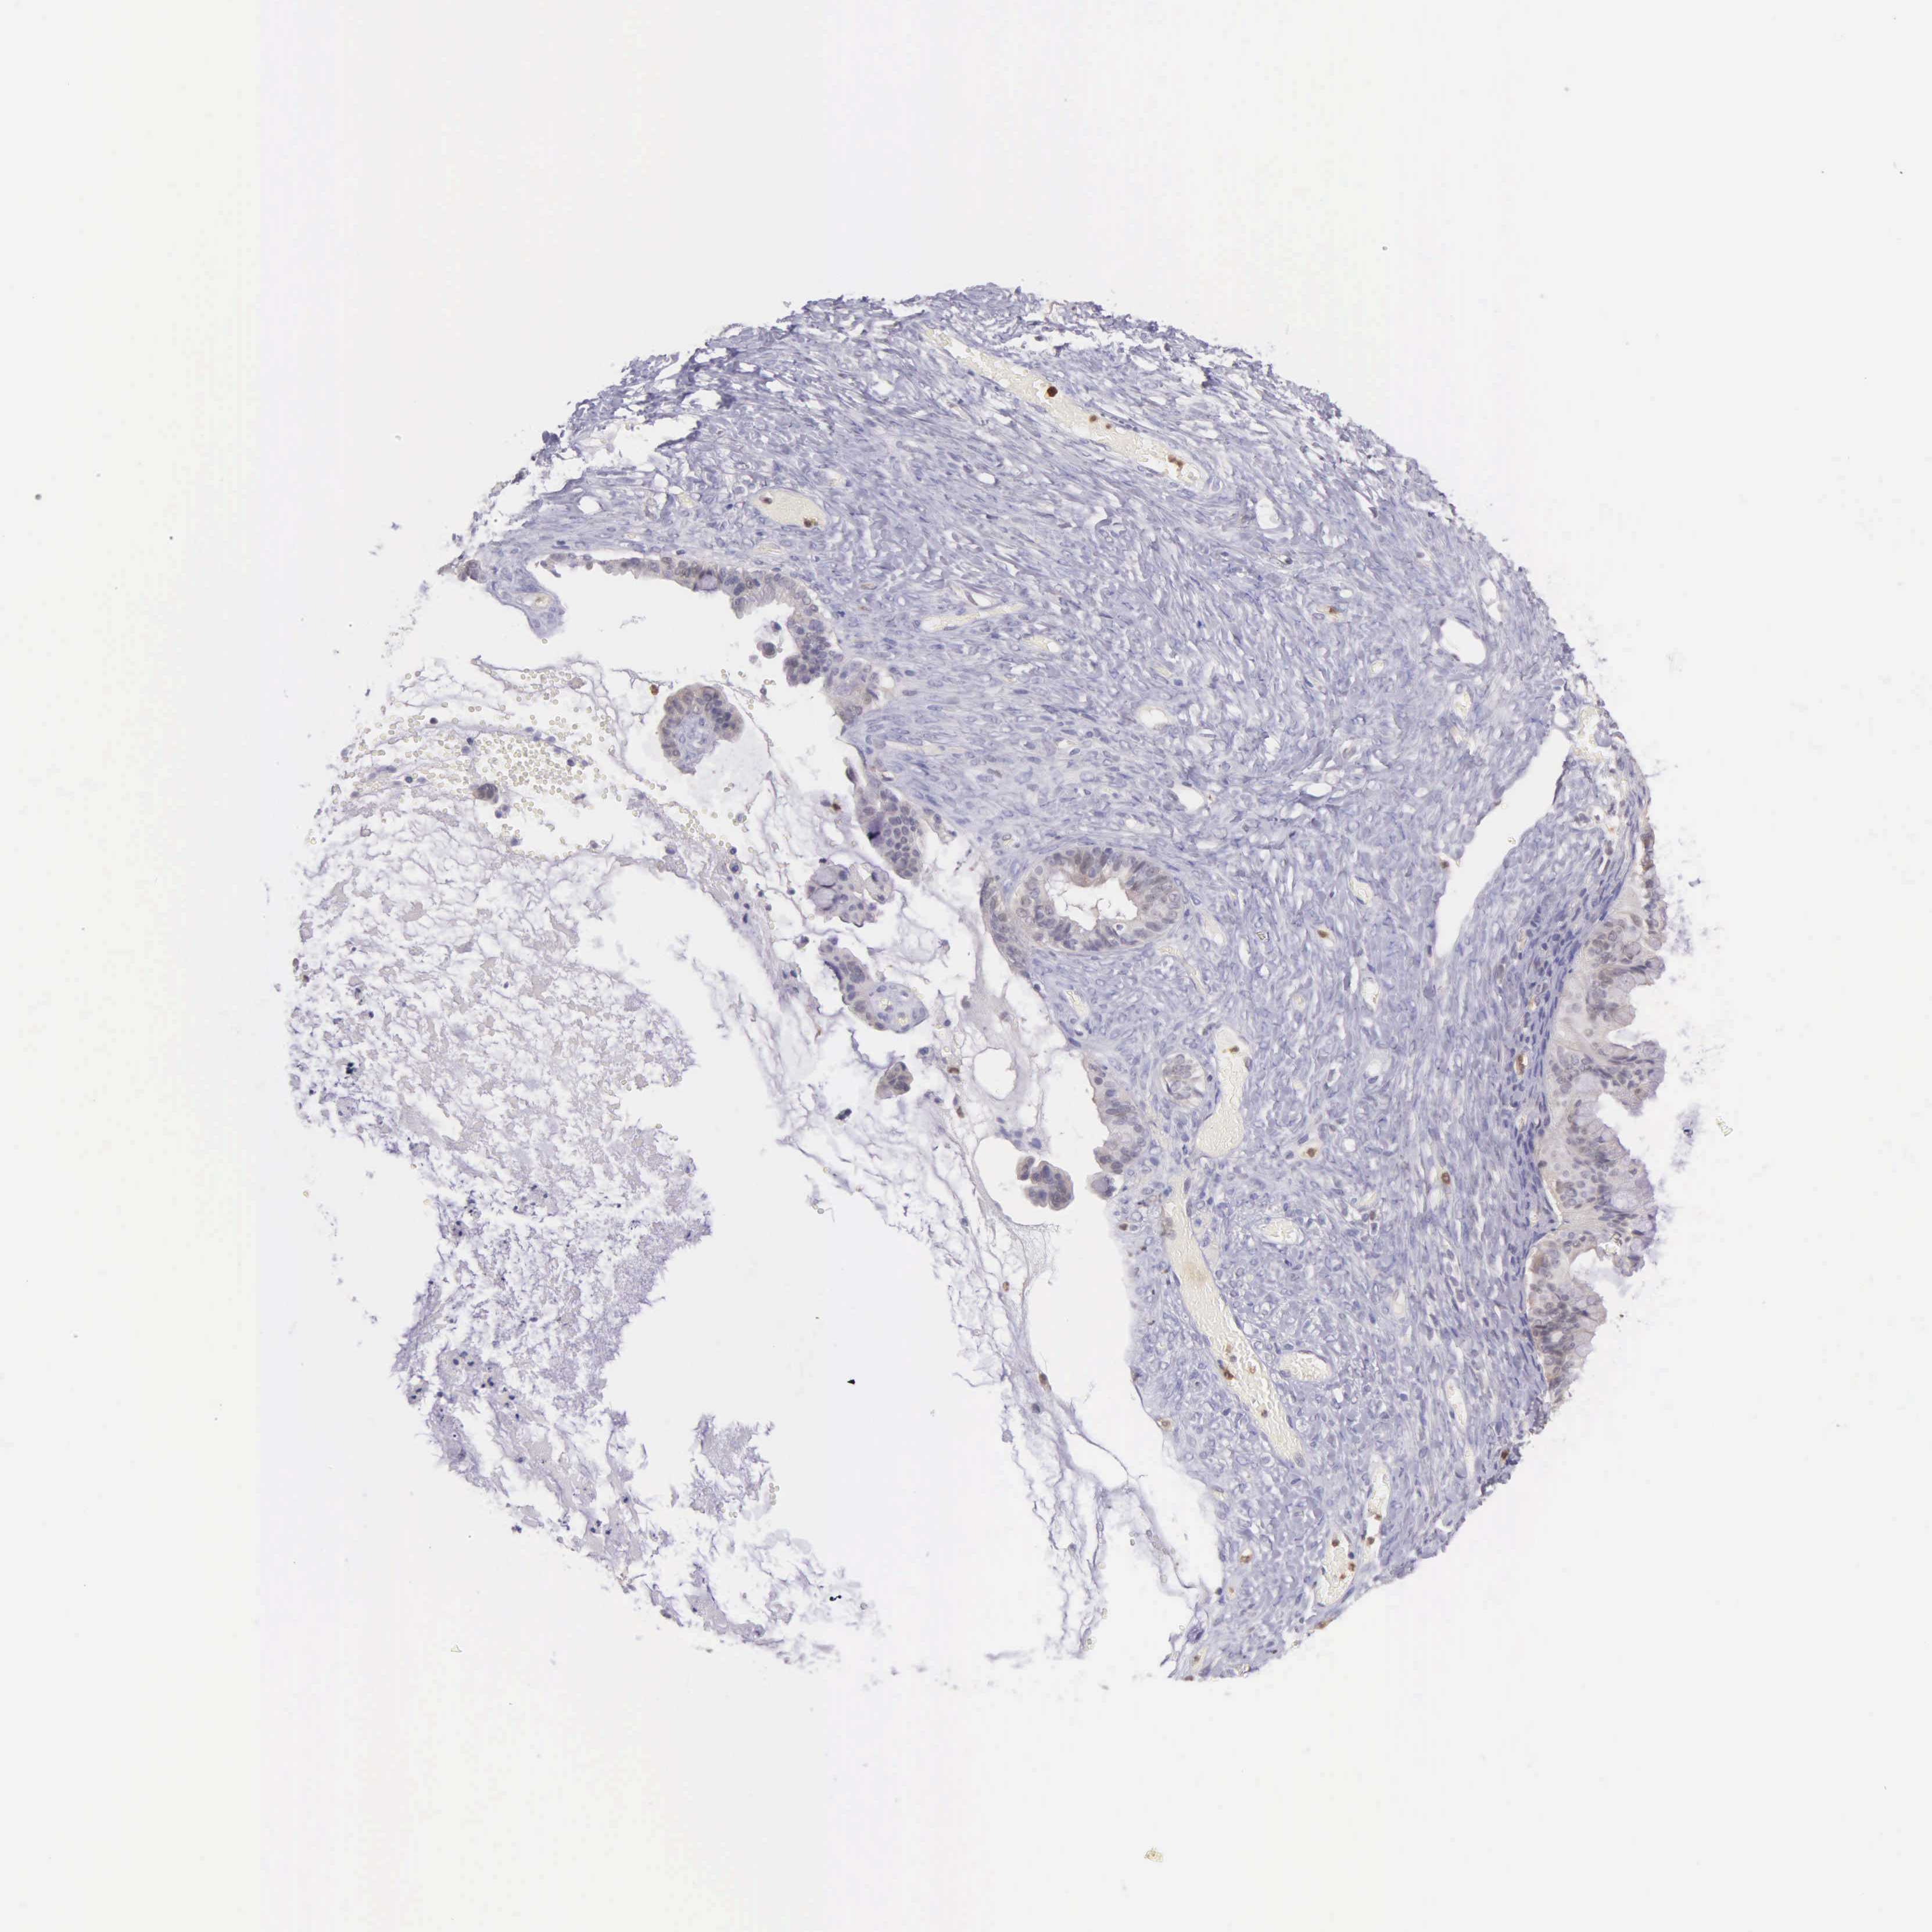

OVARIAN CANCER - Protein expressioni

A mouse-over function shows sample information and annotation data. Click on an image to view it in a full screen mode. Samples can be filtered based on level of antibody staining by selecting one or several of the following categories: high, medium, low and not detected. The assay and annotation is described here.

Note that samples used for immunohistochemistry by the Human Protein Atlas do not correspond to samples in the TCGA dataset.

Antibody stainingi

Antibody staining in the annotated cell types in the current human tissue is reported as not detected, low, medium, or high, based on conventional immunohistochemistry profiling in selected tissues. This score is based on the combination of the staining intensity and fraction of stained cells.

Each image is clickable and will lead to virtual microscopy that enables deeper exploration of all samples and also displays staining intensity scores, fraction scores and subcellular localization as well as patient and tissue information for each sample.

Antibody HPA000722

Antibody CAB003771

Cystadenocarcinoma, mucinous, NOS

Carcinoma, endometroid

Cystadenocarcinoma, serous, NOS